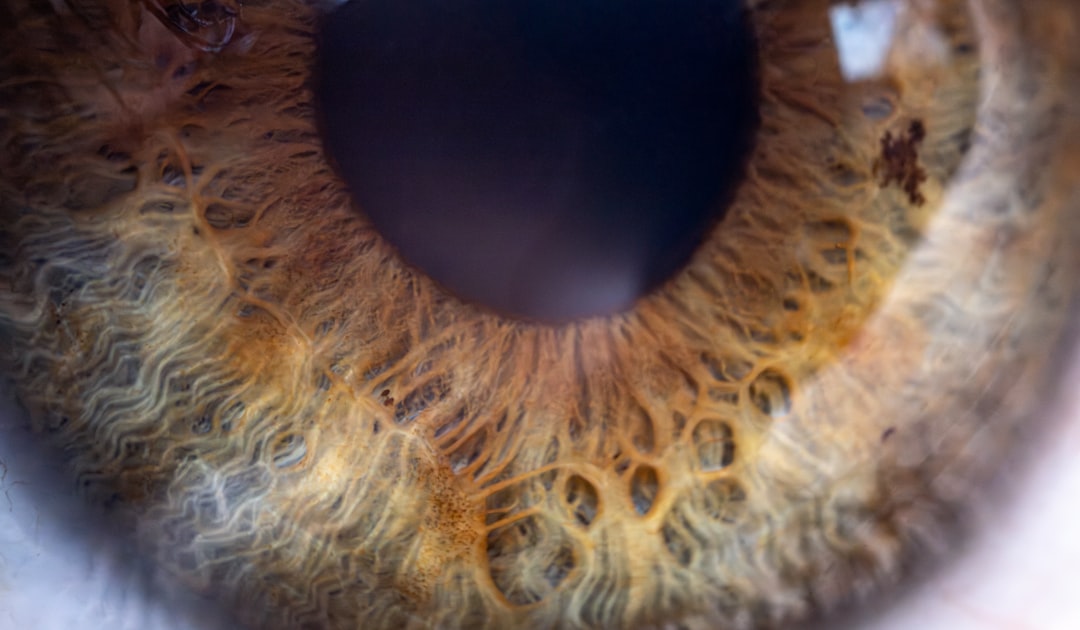

백내장은 현대 사회에서 많은 사람들에게 영향을 미치는 질병 중 하나입니다. 이러한 시각적 문제를 해결하기 위해 많은 이들이 백내장 수술을 생각하게 되며, 많은 국가에서는 이러한 수술에 대한 경제적 지원을 제공합니다. 백내장 수술비 지원 신청은 이와 같은 지원을 받을 수 있는 절차로, 여러 단계로 이루어져 있죠. 이 글에서는 백내장 수술비 지원 신청이 무엇인지, 어떻게 신청할 수 있는지를 자세히 살펴보도록 하겠습니다.